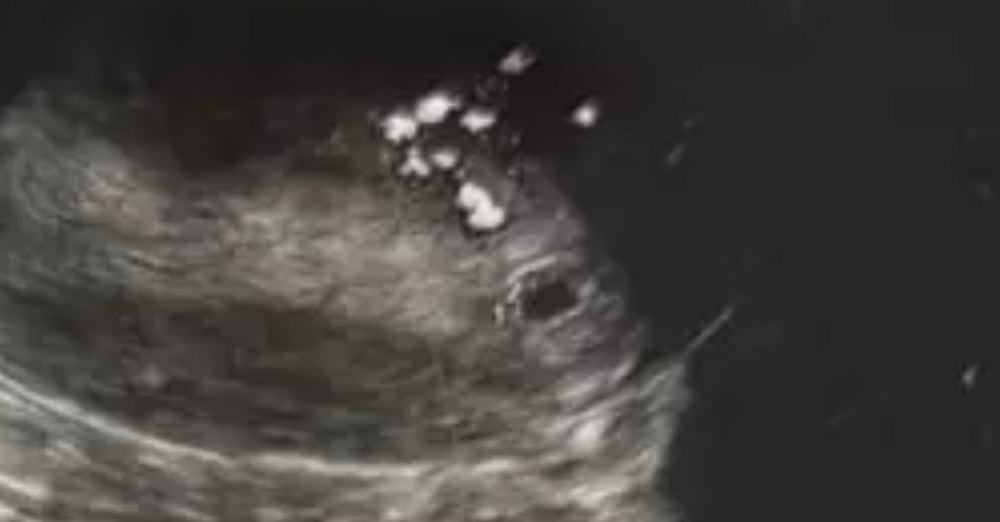

Вот мое узи при хгч примерно 1500, уже не помню, 15го сентября было узи, 17го хгч был 3500, больше не сдавала. ПЯ по узи 4,2мм 🙌🏻☺️Ваше «образование» это и есть пя. Обходите эту клинику стороной

Крис, сегодня переделала в другом месте , плодное яйцо 5 мм, увидели тут же , были в шоке от этого узи , что там понаписали , сказали картина 5 недели беременности